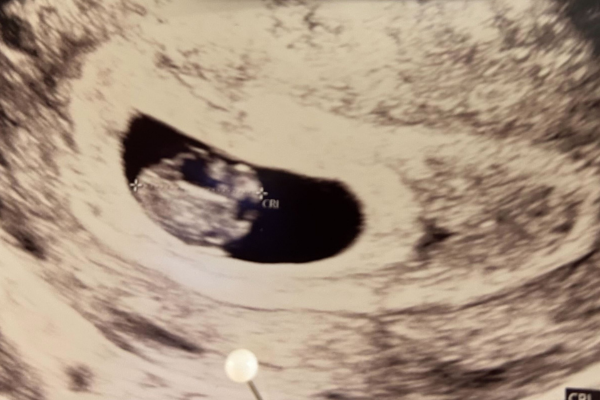

Få en tidlig scanning. Det er bare helt igennem fantastisk at opleve babyen på en scanning og se hjerteblink, det fremmer jeres tilknytning til det lille barn og gør graviditeten mere virkelig. Læs mere her